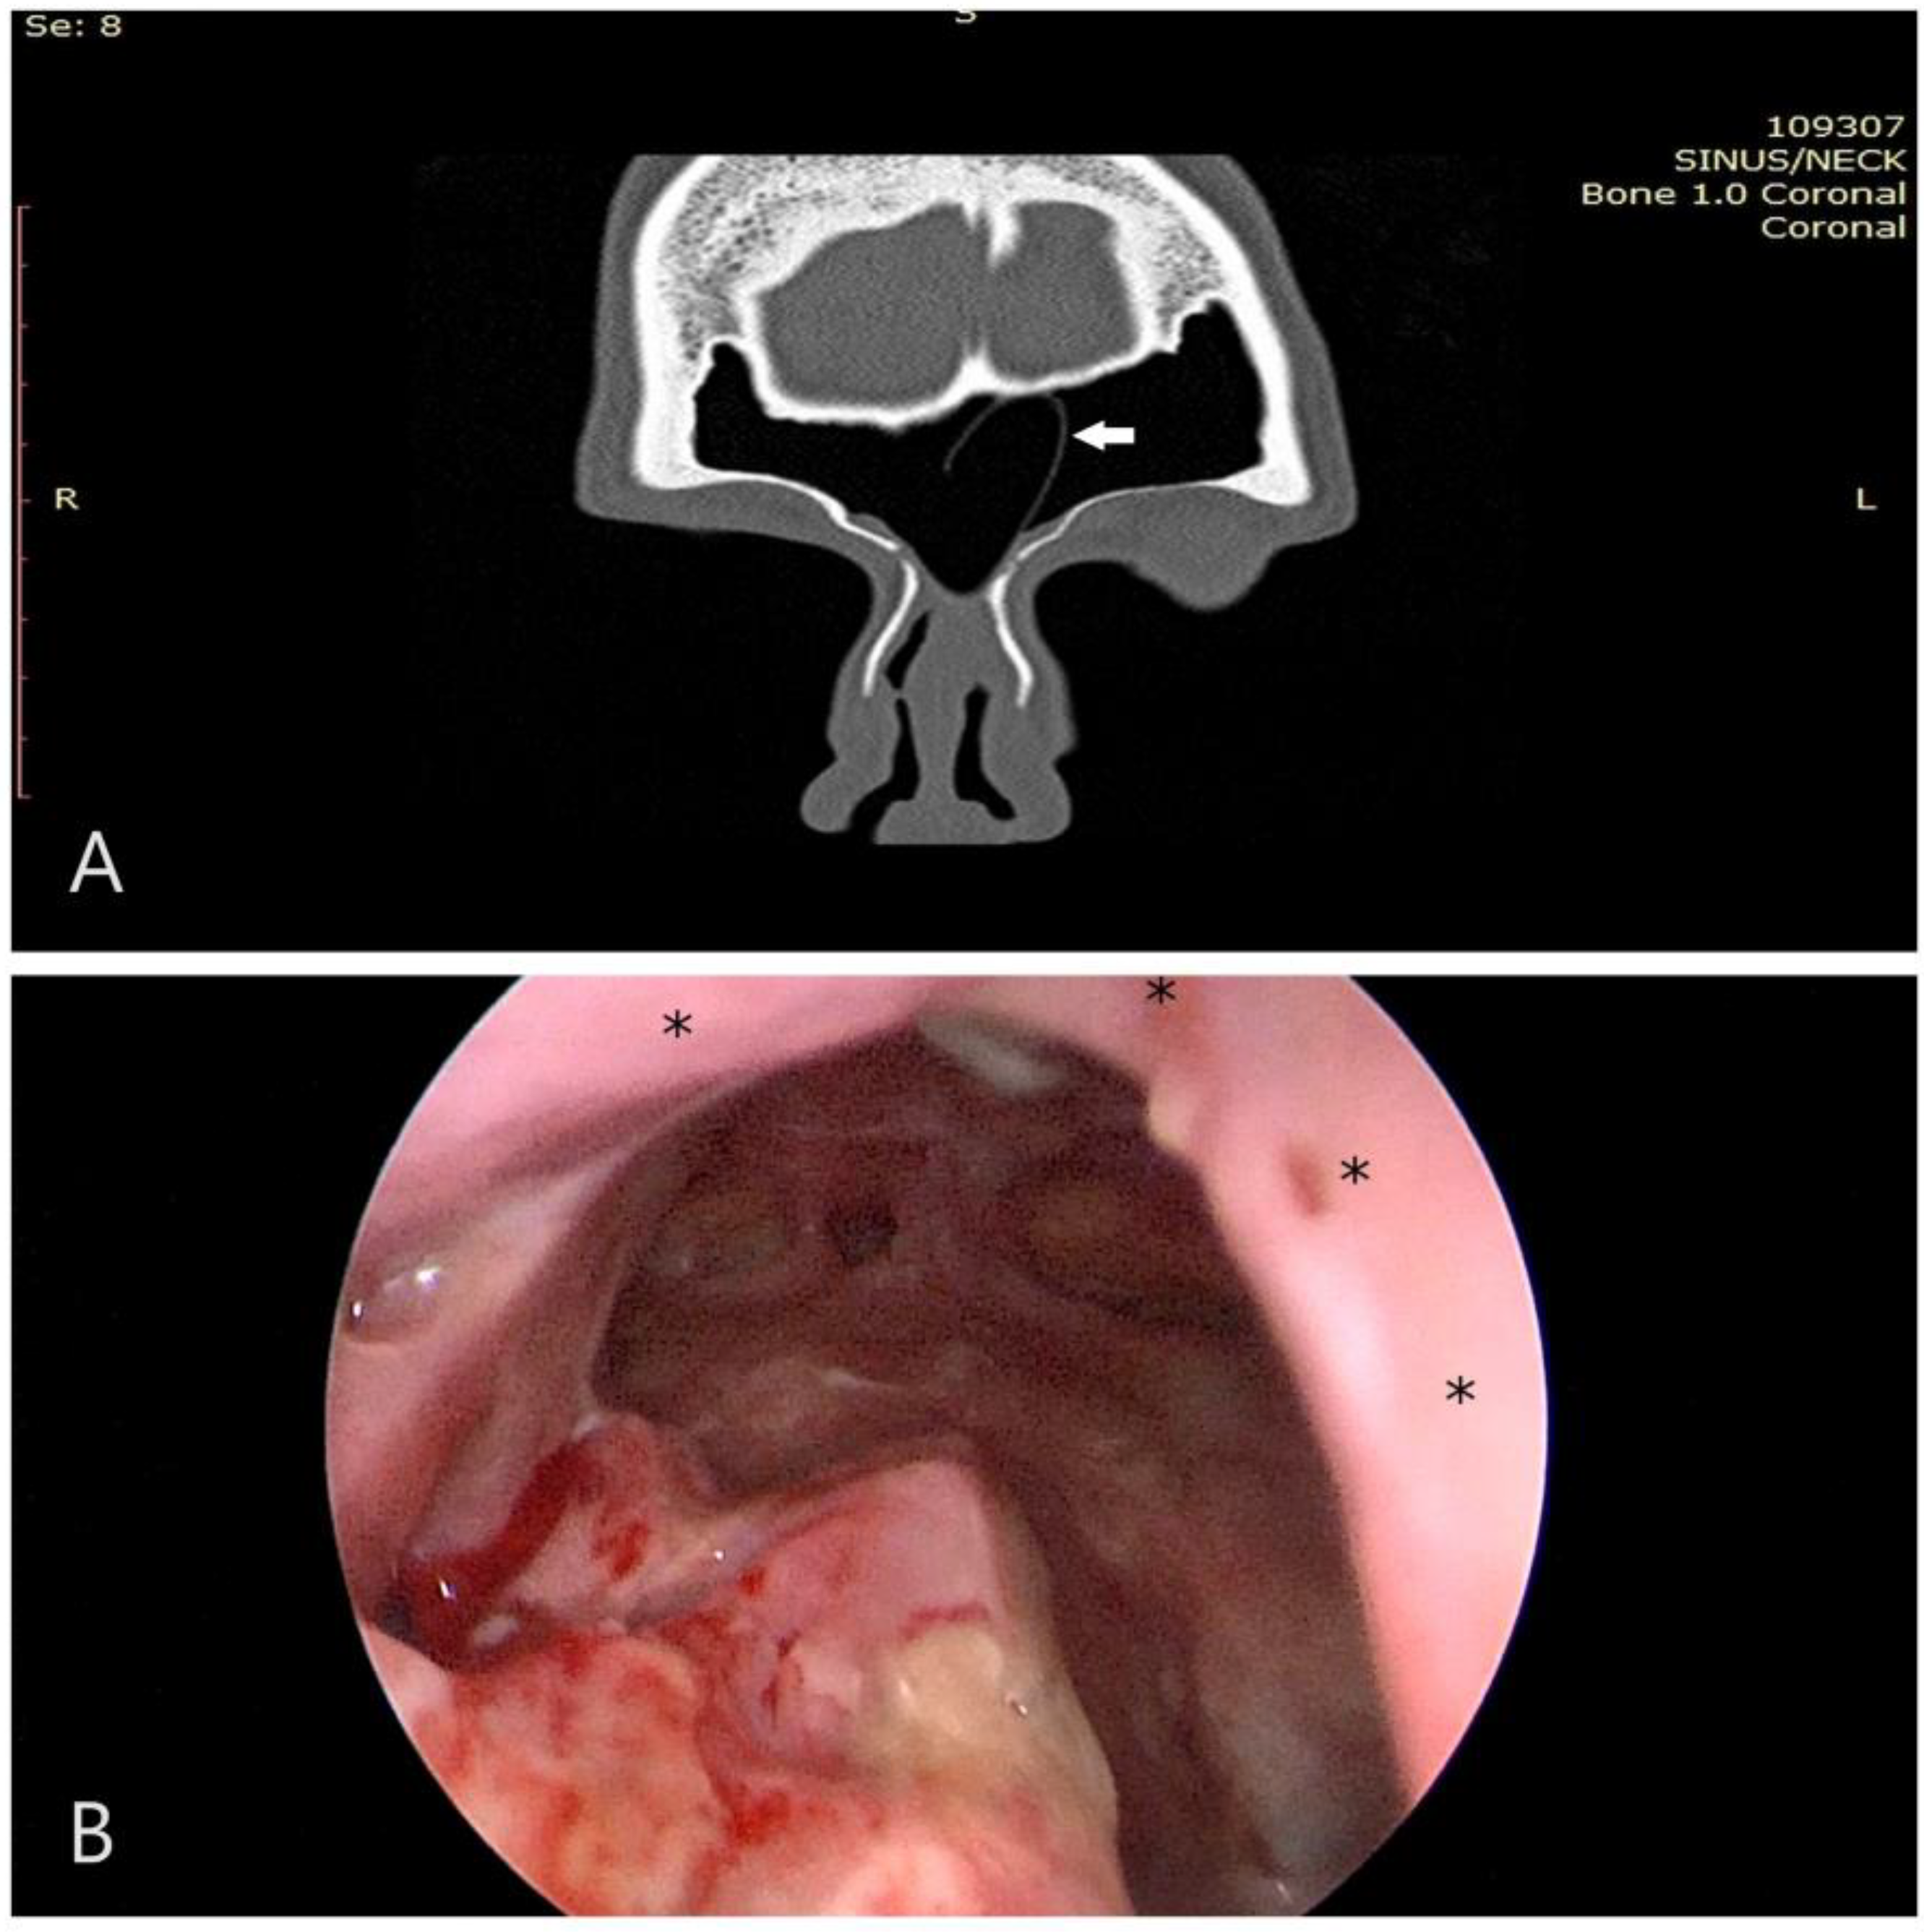

Figure 1. (A) Intraoperative perspective depicting the unified frontal sinuses subsequent to a Draf III procedure, prior to flap placement. Note the extensive bone exposure following the drill-out; (B) the laterally based flap (left side), mobilized for coverage of the exposed bone (asterisk denotes base of the flap); (C) conclusive view displaying the flap in situ (asterisks denote flap placement, green indicates neo-ostium, purple represents septal window); and (D) a 0.25 mm silastic sheet utilized to secure the flap (asterisks) postoperatively for 4–6 weeks.

In approximately two-thirds of the patients we used the lateral-to-medial (inside-out) approach, while in oncological cases involving benign and malignant sinonasal tumors we used the medial-to-lateral approach. Mucosal flaps and free grafts were utilized in 36% of cases, with the exception of malignant cases where they were never employed. Specifically, free grafts were utilized in 30.8% of cases with flaps/grafts, laterally based flaps in 61.5%, and middle turbinate septal flaps in 7.7% (Scheme 2, Figure 1).